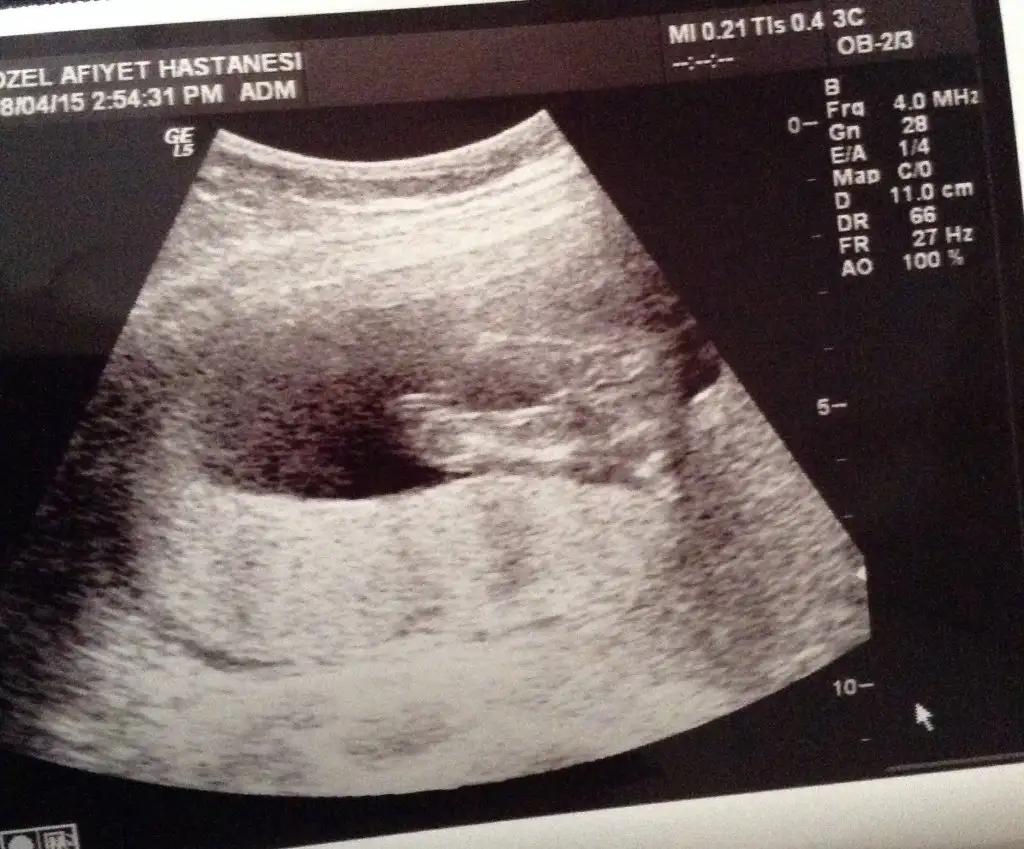

Kızlar ben de bugün ikili test için gittim. 4 gün önden gidiyoruz, 13+2'ymişiz :nazar::KK68: Doktor çok baktı bacak arasına bir şey söyledi ama kesin diyemeyiz dedi. Nub pek görünmüyor sanki, ben anlamadım. Bir de siz bakar mısınız, anlaşılıyor mu? Yoksa sonraki kontrol 4 hafta sonraaa :KK51: Allah'a şükür sağlıklı görünüyormuş ama.. bu da yeter tabii.. :KK68::nazar:

Bakın biri 10+6 fotosu biri 13+2. Dönmüş de minikim :KK46::confused: